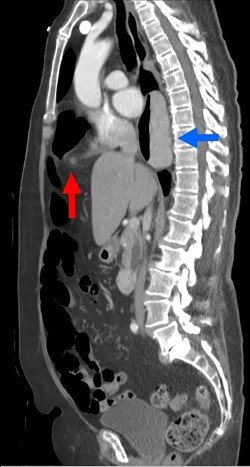

During the hospitalization, initial cardiac workup with 12-lead electrocardiogram and serial troponins was negative. The patient’s oncologic medications were held without improvement of the pain as well as to prevent leukopenia and neutropenia, if surgery was indicated. Palliative care was unable to achieve adequate pain control with oral and IV medications, and the patient did not want to pursue hospice care. Surgical consultation was obtained, and further evaluation with a CT scan of the chest, abdomen and pelvis with oral and IV contrast demonstrated an anteromedial diaphragmatic defect through which a prominent amount of mesenteric fat and a portion of the colon herniated representing a Morgagni hernia (Figs. 1–4). An increase in the size of the previously known PEH as well as the Morgagni hernia was noted. Due to continued chest pain unrelieved by opioids, a joint decision was made between surgeon, oncologist and the patient to proceed with surgery. She underwent successful robotic laparoscopic repair of the Morgagni hernia and PEH with dulex mesh for reinforcement. Her chest pain subsequently resolved. The patient gradually tolerated oral feeds and was eventually discharged in stable condition.

A sagittal view from the 2017 CT chest, abdomen and pelvis with IV and PO contrast demonstrates the Morgagni hernia with fat sweeping up through the diaphragmatic defect (red arrow) and a retrocardiac paraesophageal hernia (blue arrow).